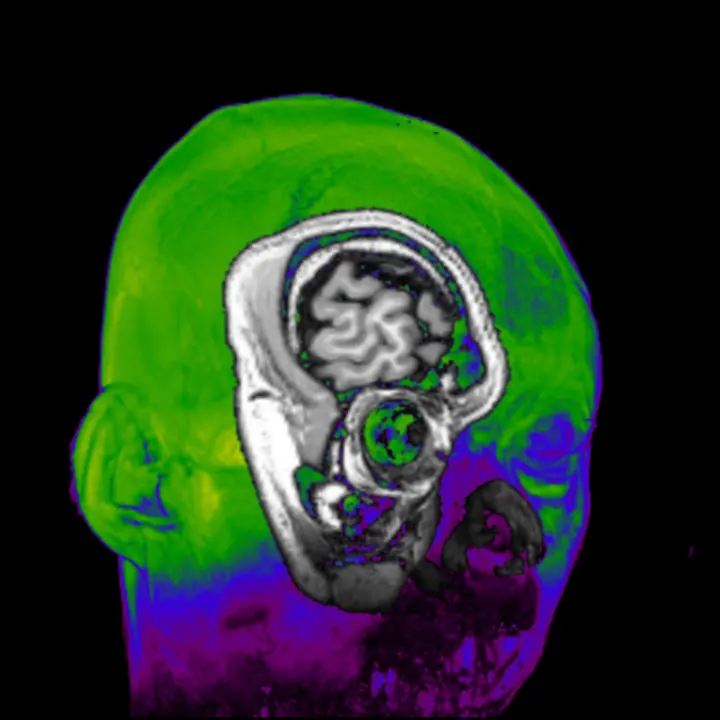

photo©Hanayuki Higashi 制作年 2018年 時間 16分(1分 x 16個) title: Daito Manabe + Kamitani Lab, Kyoto University and ATR "dissonant imaginary" 音を聴くことで変化する視覚野、連合野の 脳活動データを用いて画像を再構成する様子を可視化した作品。 マテリアル: オーディオビジュアル Kamitani Lab http:…

本作は、真鍋の3Dスキャンデータ、fMRIで取得した脳活動(視覚野)データ、そしてELEVENPLAYのダンサーとShingo Oonoによるモーションデータを用いて制作されたダンスパフォーマンス作品である。ダンスを、ポーズ/モーション/コレオグラフィーという三つの要素としてとらえ、分解し、再構築。重力や関節可動域の限界などの制約を受けない身体表現、また脳内の思考の乱れから発生するノイズやグリッチが表出し、音が脳に刺激して身体へインタ…